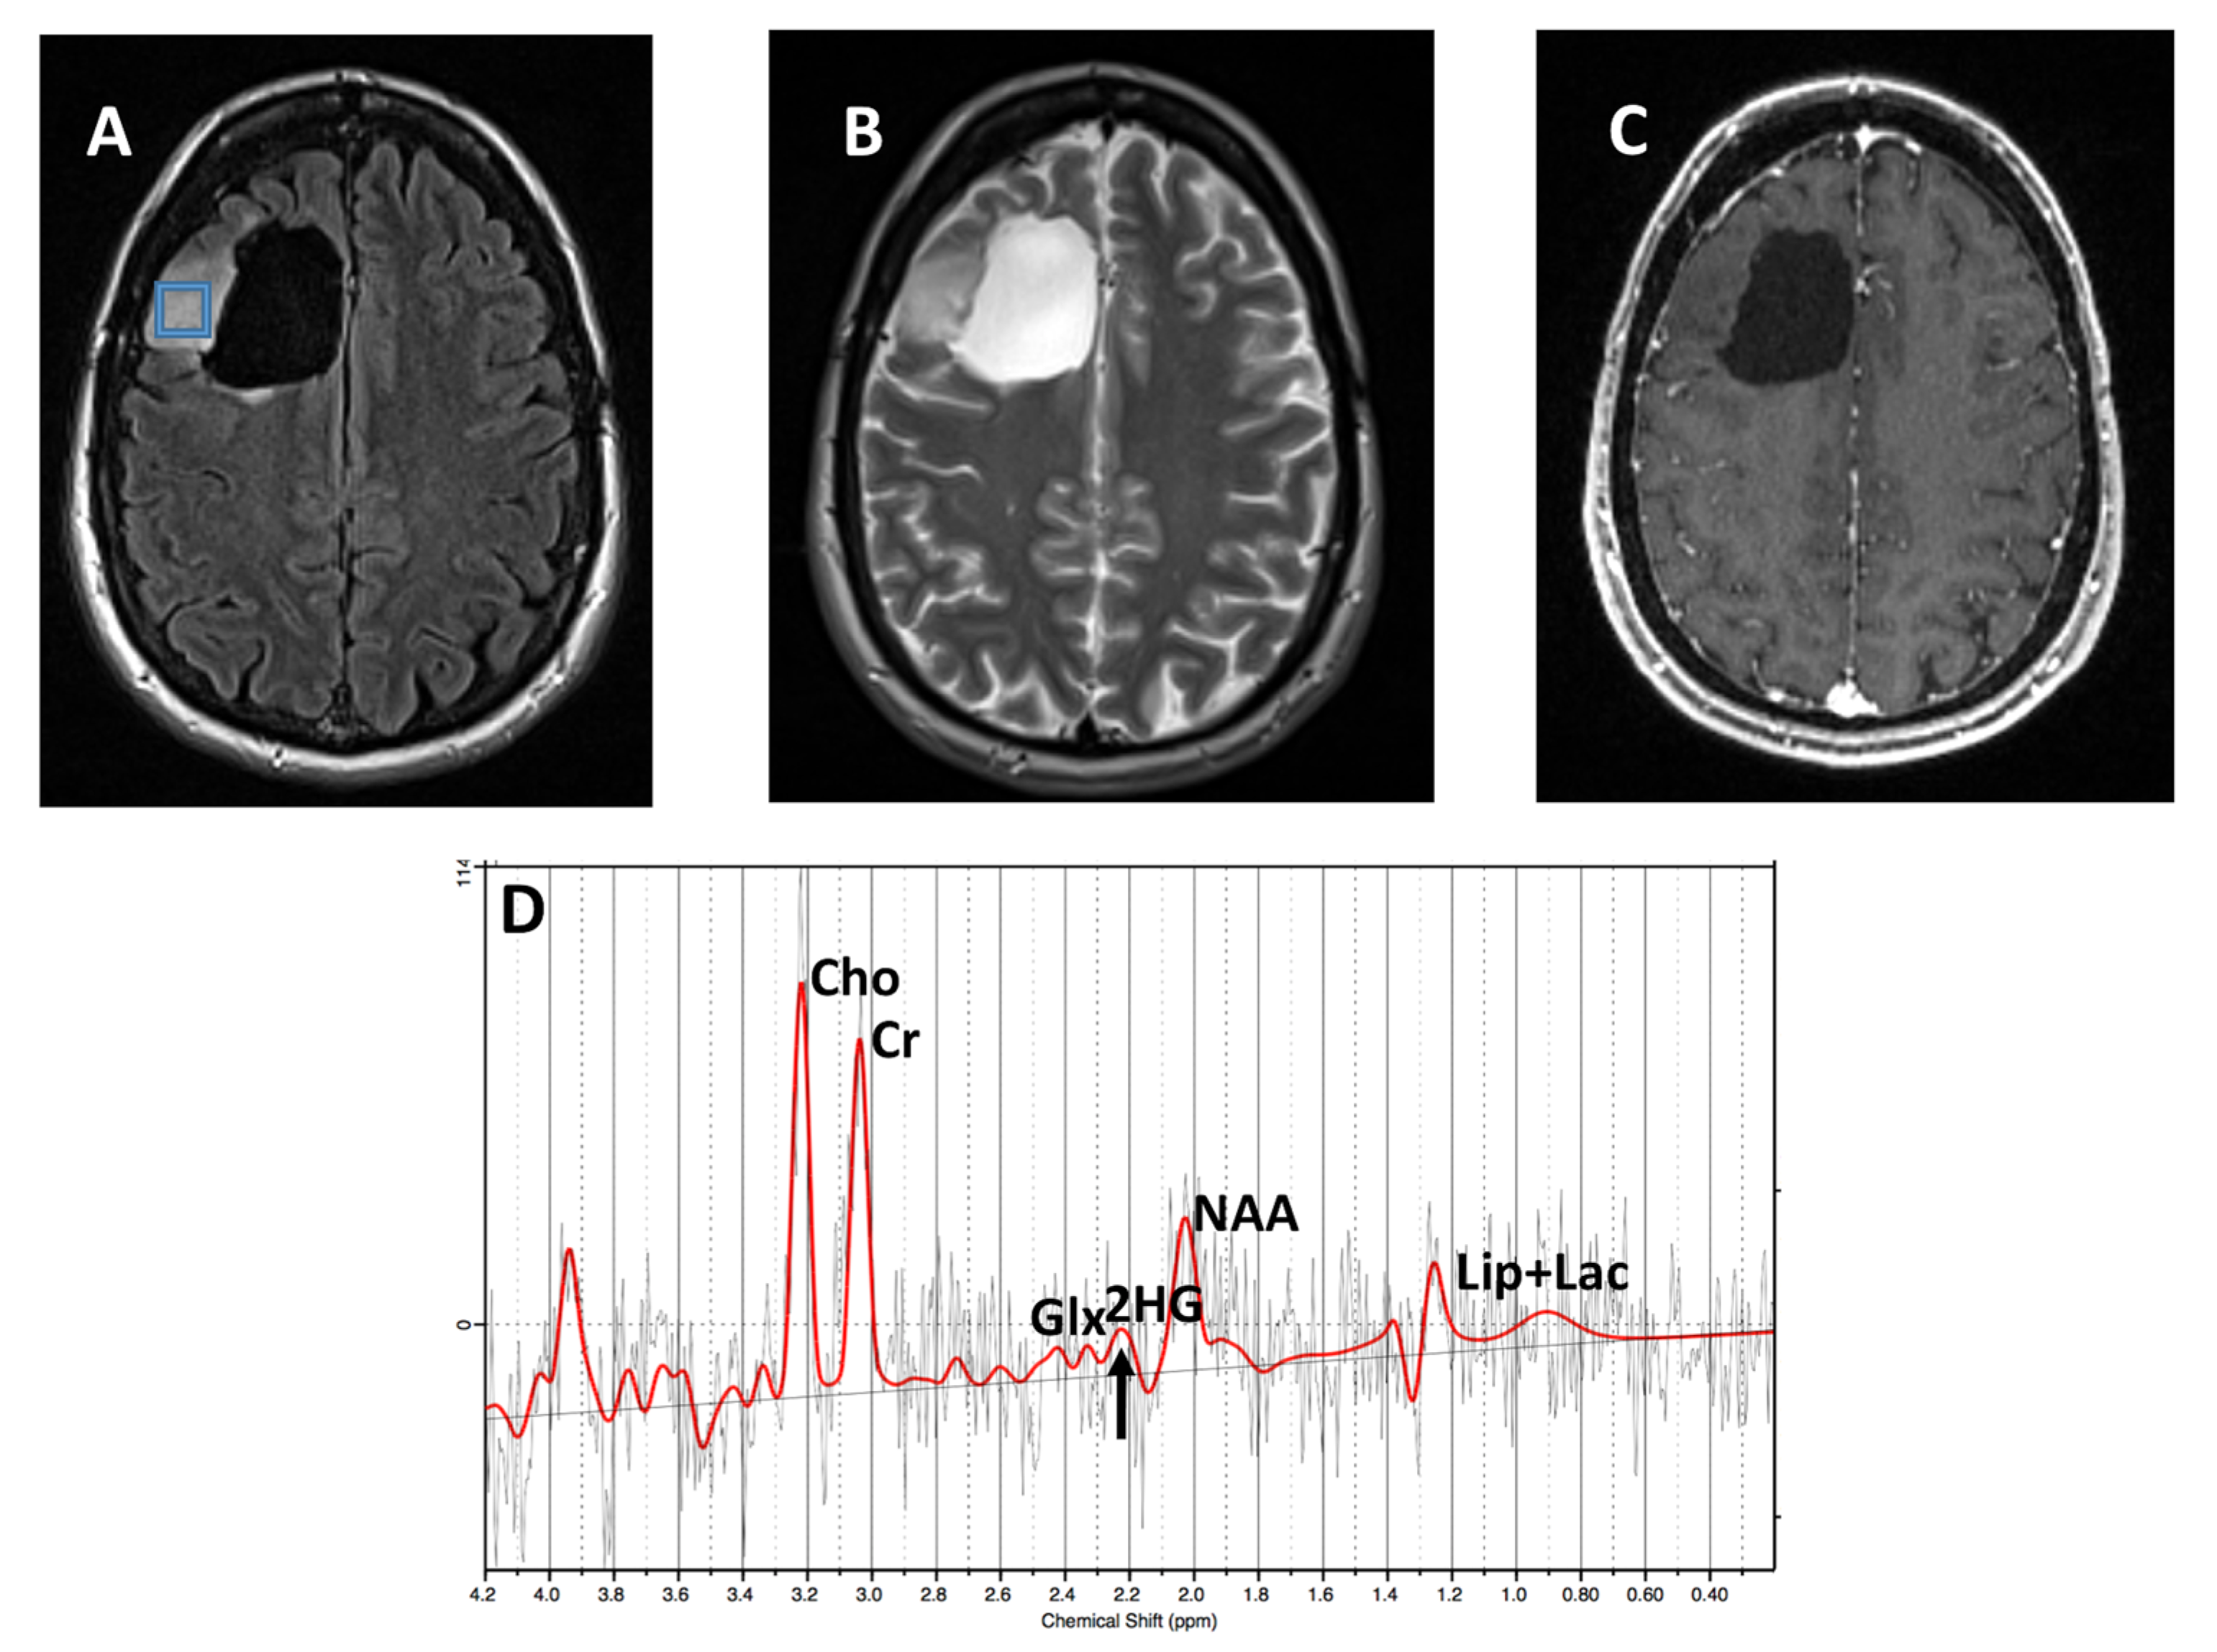

2.2. Data Acquisition

2.3. Data Processing